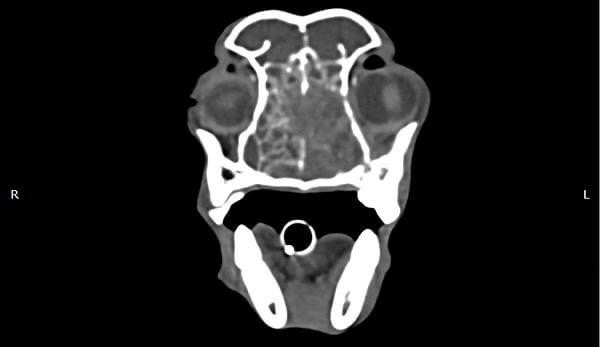

• 狗狗電腦斷層掃描 不明原因口腔出血 嚴重牙周病 口腔惡性腫瘤 鱗狀上皮細胞癌(Squamous cell carcinoma,SCC)

狗狗電腦斷層掃描 不明原因口腔出血 嚴重牙周病 口腔惡性腫瘤 鱗狀上皮細胞癌(Squamous cell carcinoma,SCC)